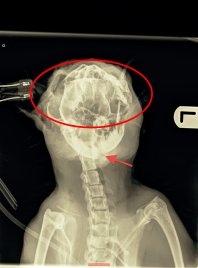

Dexter the black cat, from Redruth in Cornwall

Poor Dexter was found covered in blood in the garden, icy cold and struggling to breathe. His owners, Ruth and John Lewis, rushed him to the vets where x-rays revealed the horrific truth – Dexter had been cruelly shot through the roof of his mouth. He couldn’t walk, his jaw was broken and he had ‘shrapnel’ embedded in his head and neck.

Animal Vet Services in Hayle were able to stabilise Dexter but that was only the beginning – he had surgery to fit wires and a frame to his jaw to help it heal. He then began the lengthy road to recovery and rehabilitation. He was hand-fed for weeks, as picking up food was too painful for him, and nearly five weeks later, had further surgery to remove the metalwork.

Thankfully his jaw had healed and, three months on, Dexter has almost completely recovered from his terrifying ordeal. He is the Lewis family’s little miracle cat!